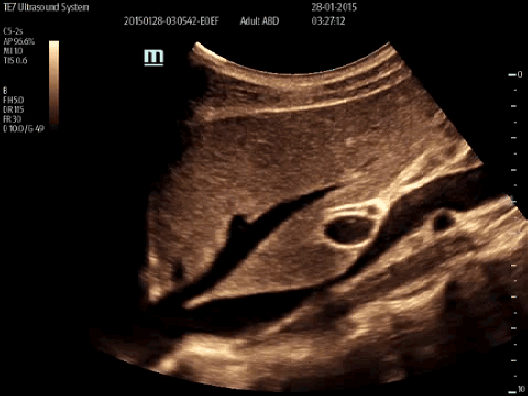

Smart IVC

Smart IVC automatycznie mierzy zapadalności żyły głównej dolnej i oblicza wskaźnik CI (Collapsibility Index) lub DI (Distensibility Index) oraz zmienność IVC, co pomaga w ocenie stanu nawodnienia pacjenta.